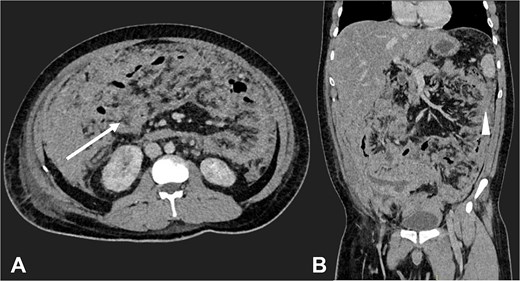

An abdominal ultrasound suggested AA (Fig. 1), prompting an open appendectomy. Intraoperative findings included cecal induration with distorted anatomy, thickened parietal peritoneum, 100 mL of ascitic fluid, and macronodular lesions on the peritoneum and intestines. Consequently, the appendectomy was not performed, and only a peritoneum biopsy and ascitic fluid sample were obtained for analysis.

Ultrasound of the right iliac fossa showing the cecal appendix (arrow), measuring 1.1 cm in diameter with a wall thickness of 0.34 cm. It demonstrated increased vascularity and non-collapsibility with compression.